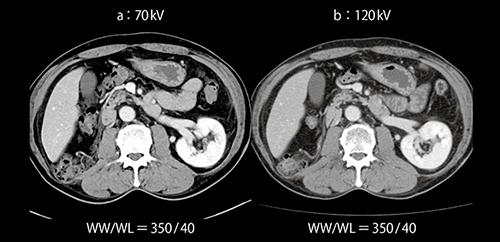

造影CTでは管電圧を下げるとCT値が上昇するため,70kVでは造影剤量を40%減量しても120kVと同等のCT値が得られ,撮影線量も若干低下する。新型X線管Vectronにより,低体重の患者はもとより,体格の大きな患者でも適用可能であった。術後片腎の患者(症例3)のフォローアップ検査においても,40%減量にて十分に良好な造影コントラストが得られた(図8)。

図8 症例3:70kVを用いた低造影剤量での腎の造影効果(体重72kg)

従来の120kVと,造影剤量を40%減量した70kVの撮影を比較したところ,肝臓,腎臓,膵臓,脾臓のいずれにおいても70kVの方がやや高いCT値が得られた。CNRも高く,造影剤量をさらに低減する余地が残っていると思われる。また,BMIが30を超えるような体格の大きな患者の肩の周囲にはストリークアーチファクトが認められることもあったが,腹部領域では問題にならなかった。